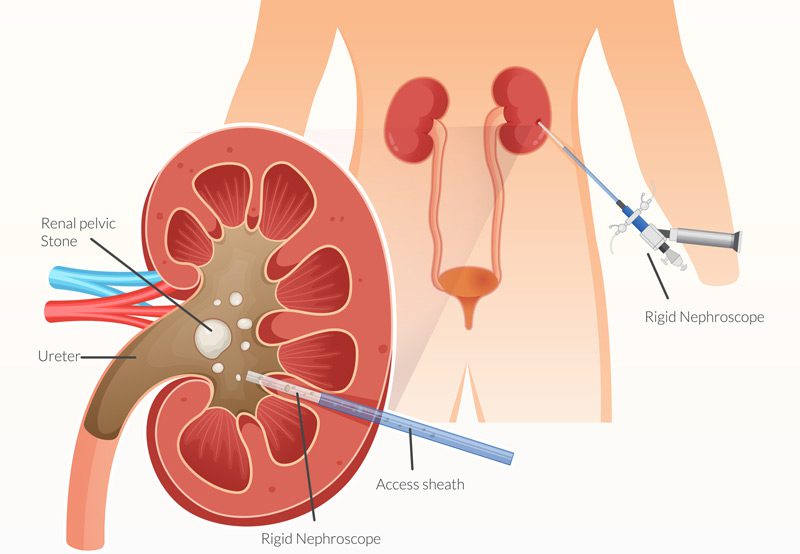

- Surgical Options: Persistent or large stones may require ureteroscopy, shockwave lithotripsy, or percutaneous nephrolithotomy (PCNL), depending on the stone’s characteristics.